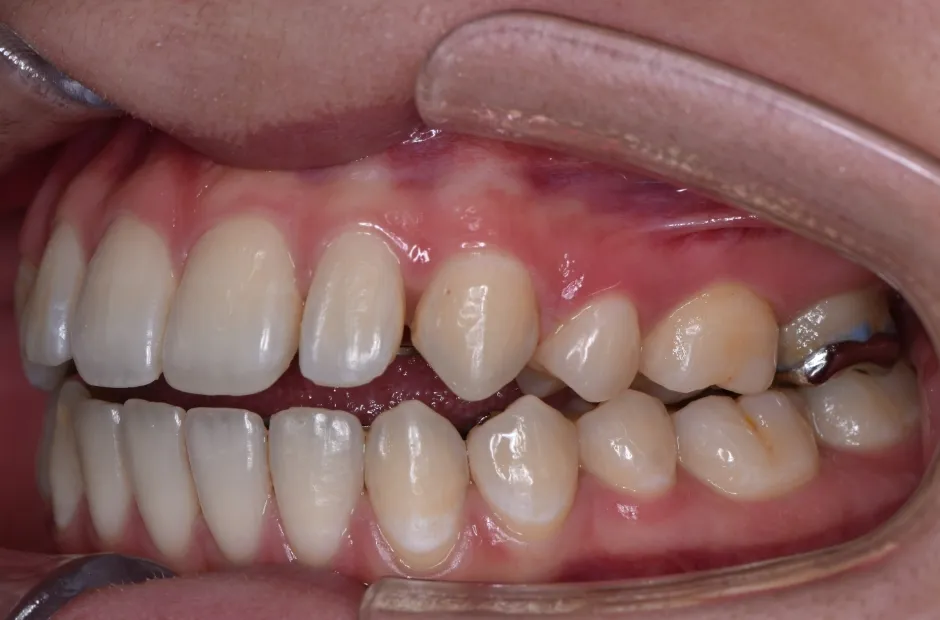

叢生

| 診断名・主訴 | 叢生 |

|---|---|

| 年齢・性別 | 43歳・女性 |

| 治療期間・回数 | 2年7か月 27回 |

| 治療に用いた主な装置 | 舌側矯正 |

| 抜歯部位 | 両顎4,4 |

| 治療費 | 100万円(税抜) |

| リスク・副作用 | 装置による違和感・疼痛・歯肉退縮・歯根吸収・虫歯のリスクなど |

治療前

治療中

治療後